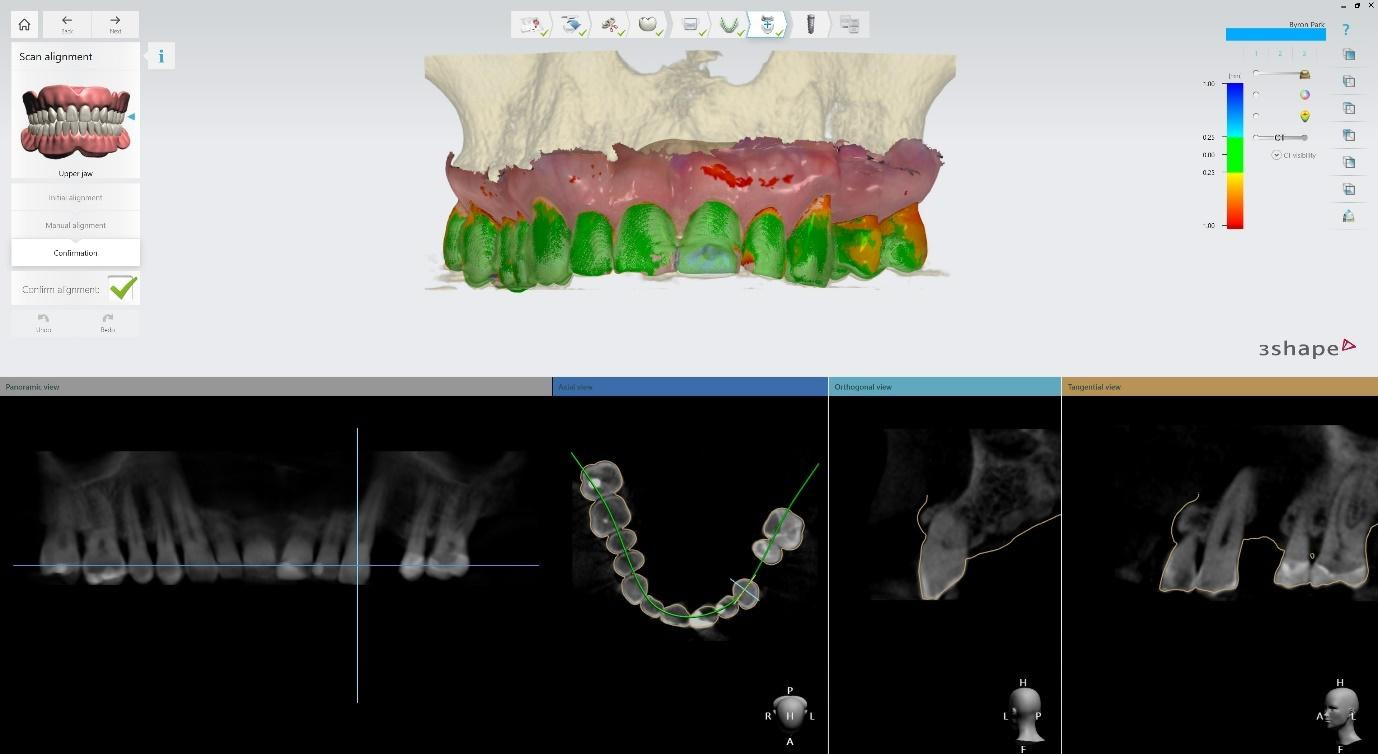

By combining data from 3shape TRIOS intraoral scans, CBCT imaging, and other diagnostic sources, TRIOS enables practitioners to visualize and create treatment plans in a fully digital environment.

Intraoral scans were completed using the Trios 4 intraoral scanner and a H8 x D 15cm craniofacial field CBCT was taken.

Pre-surgical planning began with acquiring high-quality diagnostic data, including TRIOS intraoral scans and CBCT imaging. The data was imported into 3Shape Implant Studio, where I designed a virtual crown for tooth 24 and planned the precise positioning of the implant, considering critical factors such as sinus proximity, adjacent roots, bone density, and the location of the bony defect.

Implant detection matches the scan body in the intraoral scan with the digital library. A colour scale is given to show the accuracy of the matching (Green is good).